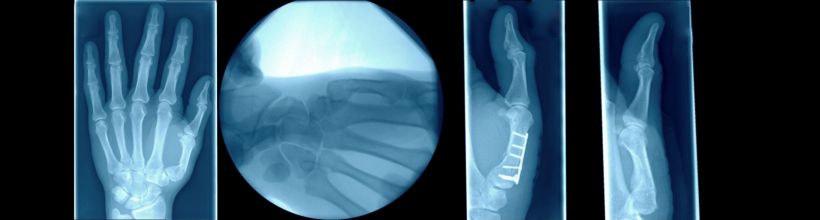

Knochenbruch am Fingerknochen oder Mittelhandknochen

Behandlung

- Ruhigstellung von außen: Oft genügt bei Knochenbrüchen ein Gips oder Cast (Kunststoffschiene), um den Knochen ruhig zu stellen.

- Stabilisierung von innen: In manchen Fällen müssen die Bruch-Enden jedoch durch Osteosynthese mit Schrauben, Metallplatten und Drähten zusammengehalten werden, damit sie wieder gut zusammenwachsen.

- oder beide Verfahren kombiniert

Osteosynthese - Stabilisierung

- anatomische Reposition: Fixierung der zueinander gehörigen Knochenfragmente in einer möglichst normalen Stellung, oft unter mildem Druck, mit Schrauben, Metallplatten und Drähten

- Stabilisierung der Fraktur, z. B. durch zwei oder mehrere Kirschner-Drähte: weniger stabil als die Osteosynthese, daher ist meist eine zusätzlich Schiene nötig; jedoch ist der operative Aufwand geringer und die OP dadurch weniger belastend.

Moderne Spezialimplantate

- Titan (gut verträglich)

- keine Allergien / Unverträglichkeiten

- winkelstabile Schrauben in der Platte für mehr Halt, auch bei weichen osteoporotischen Knochen

- weniger Schrauben erforderlich

- i. d. R. frühere Belastungsmöglichkeit (wichtig für aktive oder verwirrte Patienten)

- Wiederherstellung der Knochenform

- innere Stabilisierung für Übungsstabilität

- keine äußere Schiene erforderlich, um die Gelenkbeweglichkeiten der Nachbargelenke zu erhalten (Daumensattelgelenk sowie Daumengrund- und Endgelenk)

Metallentfernung

Wenn der Knochen verheilt ist, können die Metallimplantate wieder durch einen kleinen operativen Eingriff (Zweitoperation) entfernt werden, in vielen Fällen sogar ambulant.

Bei Kindern sollte das Material nach Abschluss der Knochenheilung in der Regel immer entfernt werden, da der Knochen noch wachsen muss.